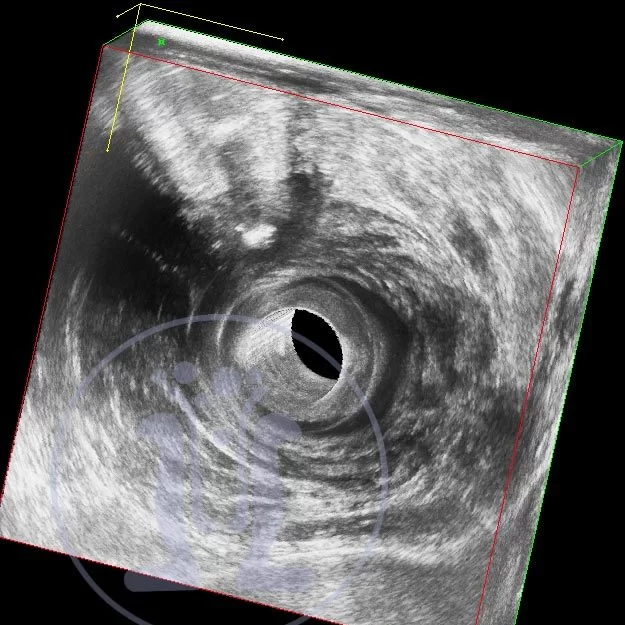

Αποτυχία πρωτοποριακής!! χειρουργικής επέμβασης για περιεδρικό συρίγγιο πάνω από 4 φορές.

O συνάδελφος είχε υποσχεθεί ποσοστό επιτυχίας 90%- καλύτερο ακόμη και από το 70% του επινοητή της μεθόδου (K. Wilhelm). Ομως η εγχείρηση απέτυχε πάνω απο 4 φορές!!!